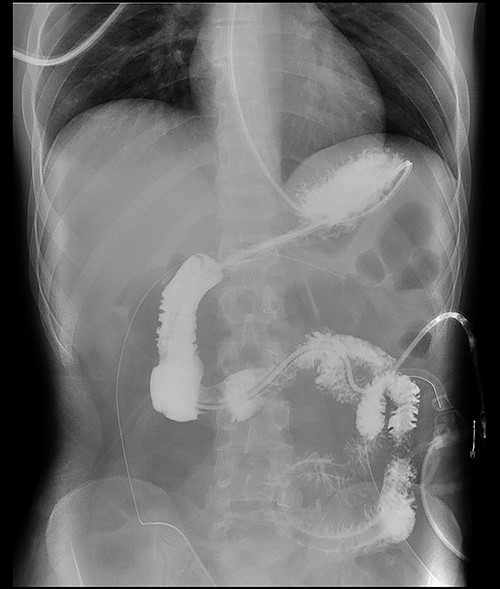

Here, we report a case of a 21-year-old man who was admitted to our hospital following a motor vehicle collision where he was a pedestrian, hit by a car and pushed against the bumper of another car. Upon arrival to the hospital, he was conscious and oriented, with normal vital signs. Abdominal examination revealed ecchymosis over the epigastric area with tenderness, however, no distention was noticed. Focused assessment with sonography for trauma result was positive in the right upper quadrant. His initial blood test results revealed a white blood cell (WBC) count of 26.5 × 109 cells/l and a hemoglobin level of 150 g/l. His serum amylase and lactic acid levels were 92 U/l and 4.53 mmol/l, respectively. His base deficit was 4.3. He underwent abdominal computed tomography (CT) with oral contrast, which showed query duodenal and possible pancreatic transection with active arterial extravasation (Figs 1–3). In addition, CT revealed a comminuted right intertrochanteric femoral fracture without associated vascular injury.

Exploratory laparotomy was performed, which revealed ~500 ml of blood in the peritoneal cavity, central retroperitoneal hematoma, peripancreatic hematoma and complete transection of the third part of the duodenum. The retroperitoneal hematoma and peripancreatic hematoma were nonexpanding. A formal end-to-end anastomosis of the third part of the duodenum was performed using 3–0 polydioxanone (PDS) in a single layer. Double decompression of the duodenum was achieved using a nasoduodenal tube (ND) and a retrograde duodenostomy tube. A jejunostomy tube was created for feeding as well.

Postoperatively, the ND and retrograde duodenostomy tubes were maintained on continuous suction. Feeding through jejunostomy tube was initiated on postoperative Day 2, and the ND tube was removed on postoperative Day 23 when oral feeding was initiated. Although postoperative CT and Gastrografin swallow confirmed good anastomosis without evidence of leaks (Figs 4–7), The prolonged hospital stay and the delays in removing ND tube and initiation of the oral intake was because of persistent sepsis and high WBC counts, which was later confirmed to be secondary to abscess in his right thigh.

Despite its limitations in distinguishing between duodenal hematoma and duodenal perforation, CT with intravenous and intraluminal contrast remains the gold standard diagnostic test in stable patients with blunt abdominal trauma [1]. In the reported case, CT revealed duodenal and possible pancreatic transection with active arterial extravasation.